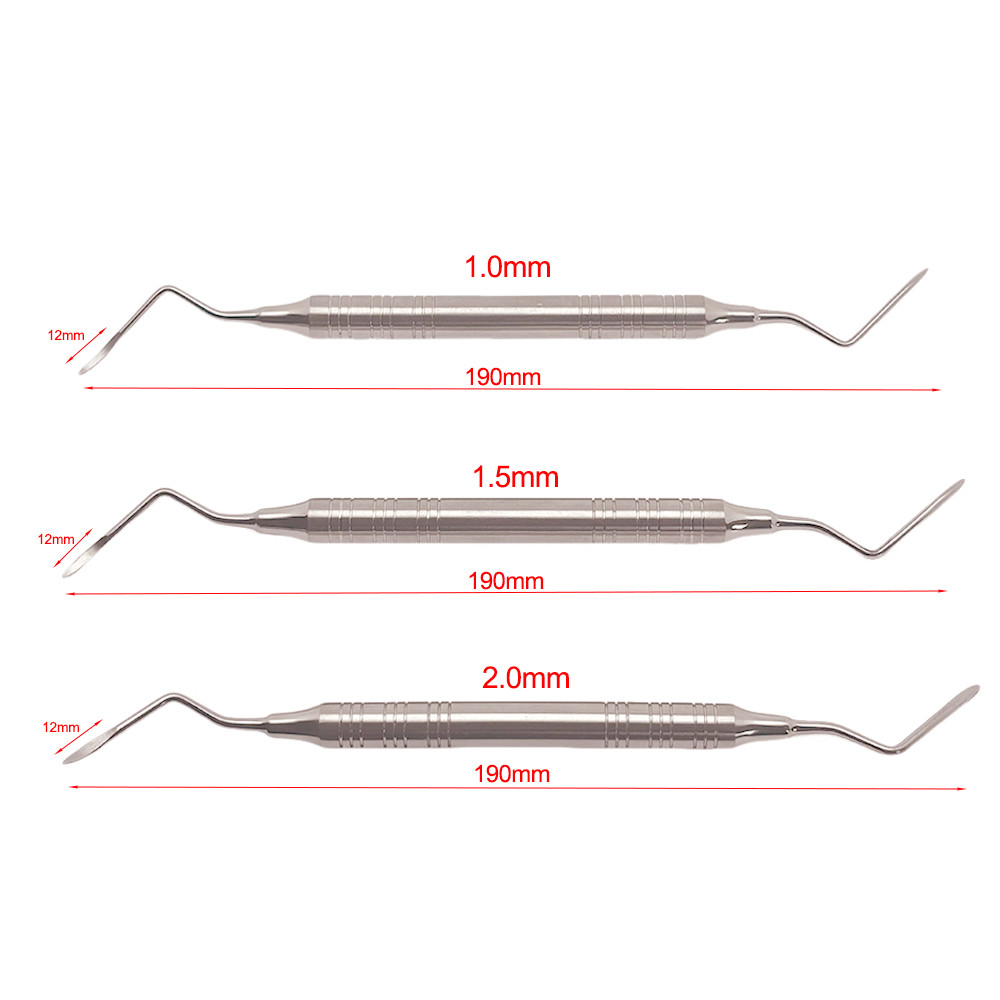

3 Variations Available

Dental Minimally Invasive Extraction Tool Root Tip Pick Elevator with Sharp Tip for Dental Implant Tooth Extraction Surgical